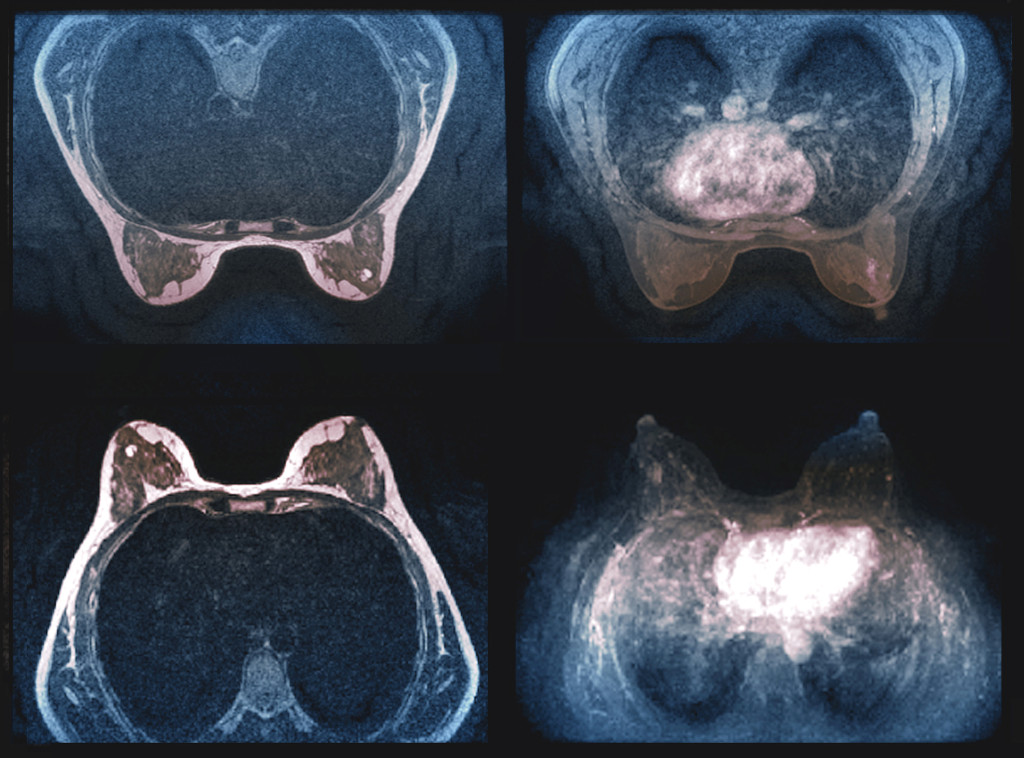

Illustrasjon: Science photo library / NTB Scanpix